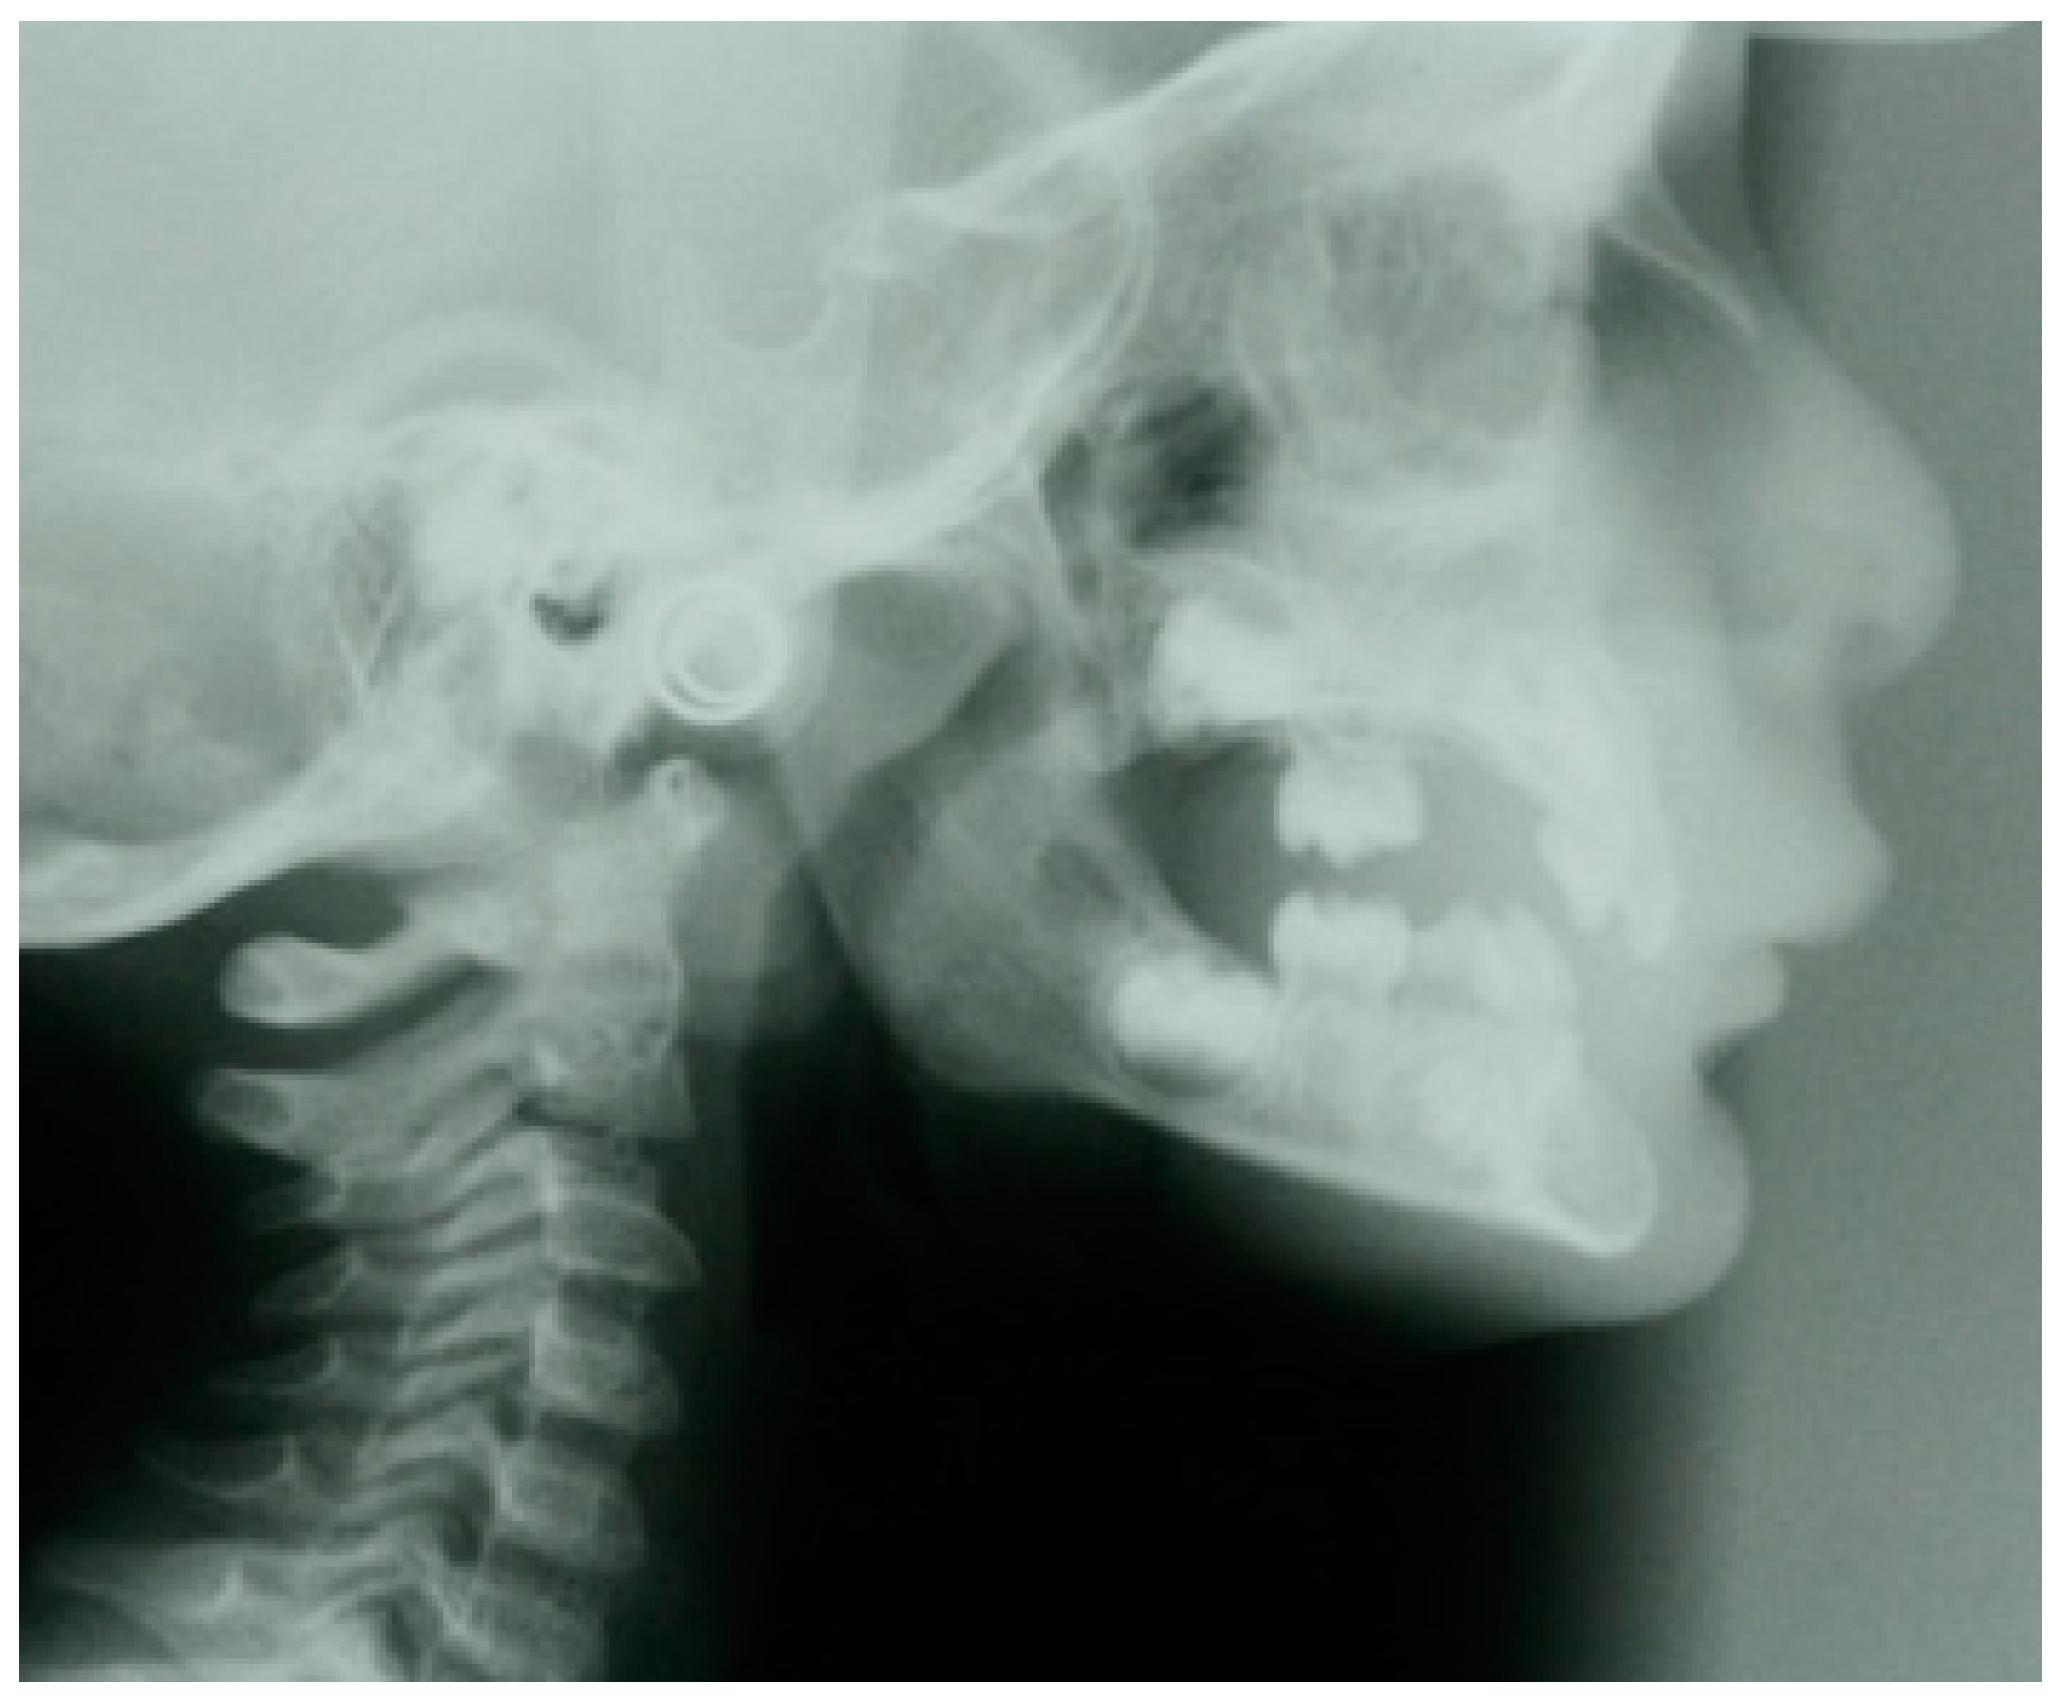

- Sasaki, Y.; Kaida, C.; Saitoh, I.; Fujiwara, T.; Nonaka, K. Craniofacial growth and functional change in oligodontia with ectodermal dysplasia: A case report. J. Oral Rehabil. 2007, 34, 228–235. [Google Scholar] [CrossRef]